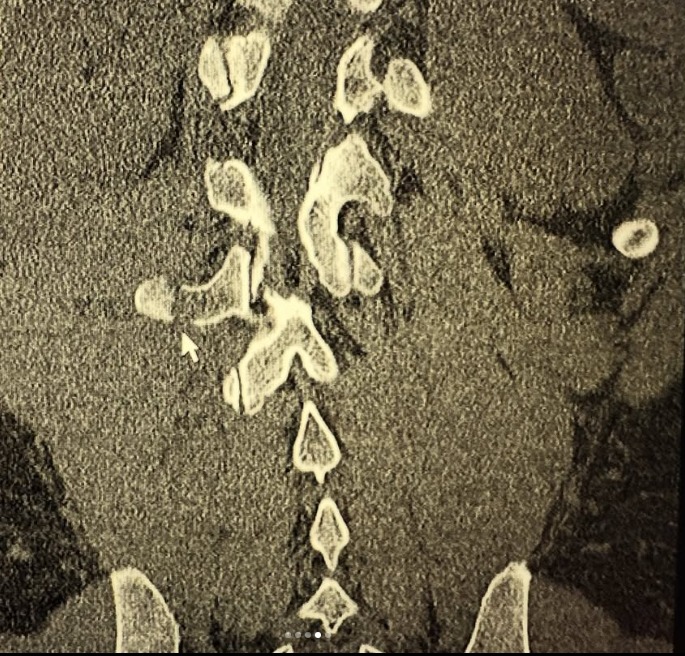

Tuesday night Sergio had a bicycle accident. He took a corner going 30 mph+, pedaled down and clipped the pavement launching him over his handlebars and flat onto his back. He broke the transverse process of L2,3,4.